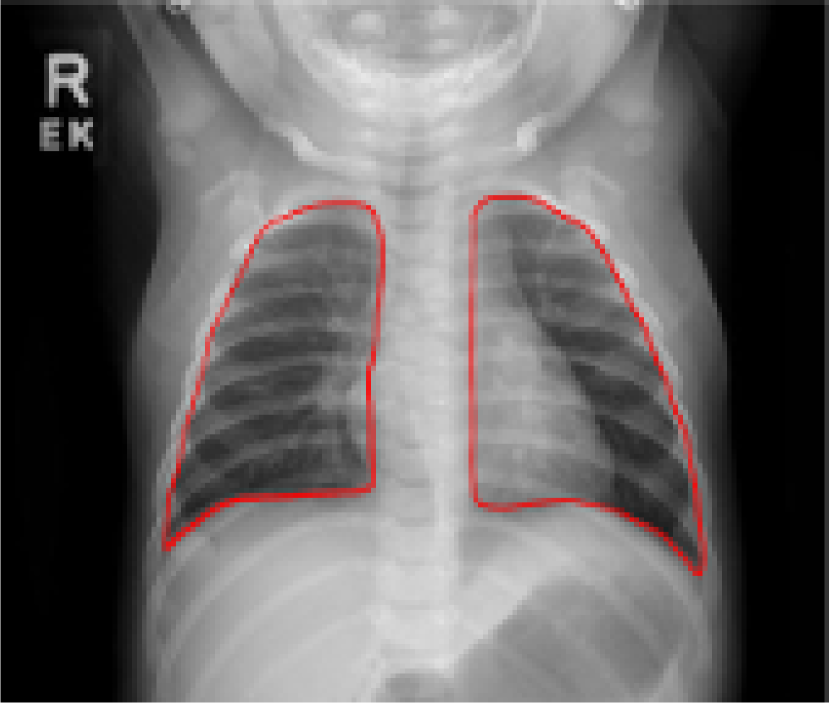

Despite tremendous advancements in tomographic imaging, chest radiography remains the most commonly used imaging modality for pulmonary analysis mainly due to its low cost, low radiation dosage, and widespread availability. Radiation dosage is of particular concern in pediatric applications, especially in neonatal intensive care units where chest radiographs (CXRs) are considered the first option for pulmonary diagnosis [1]. Lung field segmentation is the necessary initial step for image-based pulmonary analysis. Accurate delineation of lung field from CXR, however, is challenging due to ambiguous boundaries, pathologies, occultation of lung field by anatomical structures in thorax, anatomical variation of lung shapes, and size across subjects (Fig. 1). Part of the challenge in developing computer-aided diagnosis (CAD) methods, especially for pediatric cohorts, is also the anatomical shape variation of lung field that occur during growth [2, 3]. As shown in Fig. 1, pediatric cohorts have a more compliant chest wall, small thoracic cage, and relative large abdominal space. Furthermore, the diaphragm of children has smaller apposition area which has a concave shape in the posterior-anterior (PA) view CXR [3]. Therefore, existing approaches to lung field segmentation that are designed primarily for adult cohorts, are not accurate at analyzing the pediatric subjects. Although a few pilot studies such as [2] have been conducted recently to look at the age-related radiological biomarkers in lungs, no comprehensive study of pediatric lung field segmentation exists to the best of our knowledge.

Fig. 9 presents the qualitative results of performing the lung segmentation using the proposed pipeline (ESL+MaShDL). The figure provides a visual insight on how inclusion of retro-cardiac region results in the segmentation label that is independent to the shape and structural changes in the close-by anatomical structures such as heart. For comparison purposes, similar qualitative results for the lung field labels obtained using the method proposed in [11] are provided in Fig. 10. As predicted before, the shape specificity is not preserved for the lung field labels obtained using [11]. This is further evident through the results presented in Table II. Moreover, unlike the proposed method, the U-net architecture uses an overlapping-based objective function (e.g., cross-entropy) which provides satisfactory results in cases with reduced shape variability. However, in the particular case of thoracic radiographs, the lung field labels without retro-cardiac space present higher shape variability than those observed when including this region. This could be a possible explanation of a slightly better overlapping-based performance (i.e., Overlap and DSC) by U-Net [11] when including the retro-cardiac space than without including it.